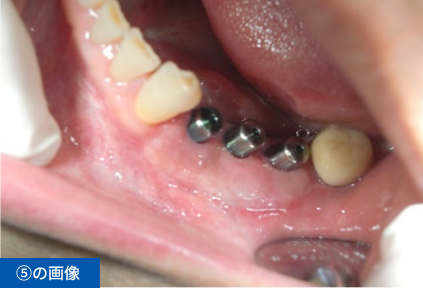

左下④56⑦番のブリッジの脱離にて来院(④⑦はブリッジの支台歯56は欠損)

| 費用 ※保険外診療 | 総額1,485,000円(税込) インプラント3本、手術2回、CGF、遊離歯肉移植、CT撮影、被せ物の型取り(印象)、被せ物(フルジルコニア)3本、投薬 |

| 想定されるリスク・副作用 | ・術後、痛みや腫れが生じる可能性があるが腫れは3日後がピークで徐々に治まる ・清掃状態が悪いとインプラント周囲炎(歯周病)を起こす可能性がある |